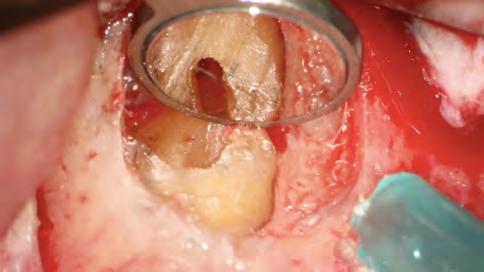

Se inició la terapia endodóntica del diente 21. Después del acceso, el conducto fue irrigado con Hipoclorito de Sodio al 5%, seguido de EDTA al 17%, ambos con PUI y Easy clean. A través del uso del microscopio operatorio, fue posible visualizar la extensión de la cavidad reabsortiva (Figura 5). Durante la preparación químico-mecánica hicimos una irrigación abundante con sustancias químicas auxiliares con capacidad solvente orgánica efectiva y punta de ultrasonido esférica para remover y diluir el tejido pulpar remanente.

Figura 5 - Cavidad reabsortiva